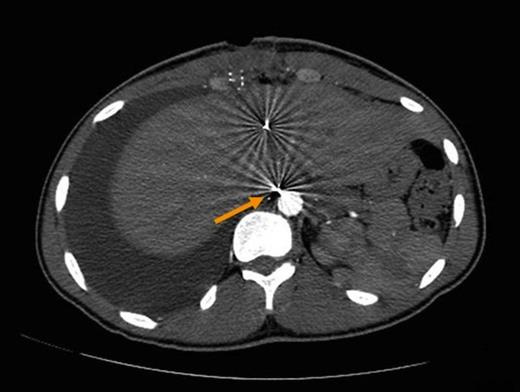

An 18 year-old-male patient presented to our trauma center following a gun shot wound to the abdomen. On arrival, he was found to have a penetrating injury to the epigastrium with no apparent exit wound. He was hemodynamically stable and a CXR demonstrated a metallic foreign body in the upper abdomen. On physical exam, he was tender to palpation. The patient was taken to the operating room for an emergency laparotomy. During surgery, a laceration of the liver was identified and repaired with omental packing (Figure 1). A large bullet fragment was palpable within the injured segment of liver and was removed. The patient had an uneventful recovery and was discharged home on post-op day 3.

Liver injury with cavitary defect (A). Repair with Omental packing (B).

Computerized tomography of the abdomen demonstrating tiny metallic fragments within liver. Fragment adjacent to aorta suspected of injuring retroperitoneal thoracic duct (arrow).